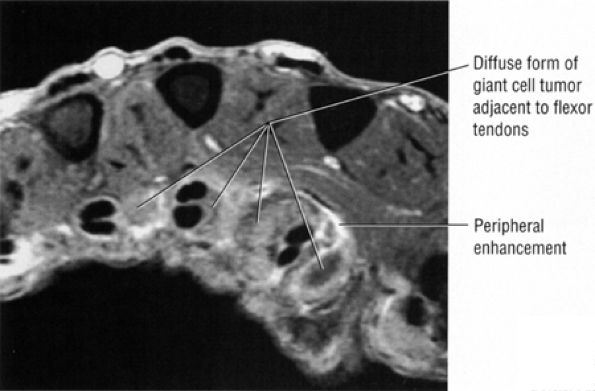

Associated dorsal ganglions in the dorsal or dorsal/membranous scapholunate ligament pathology (Fig. 10.100).